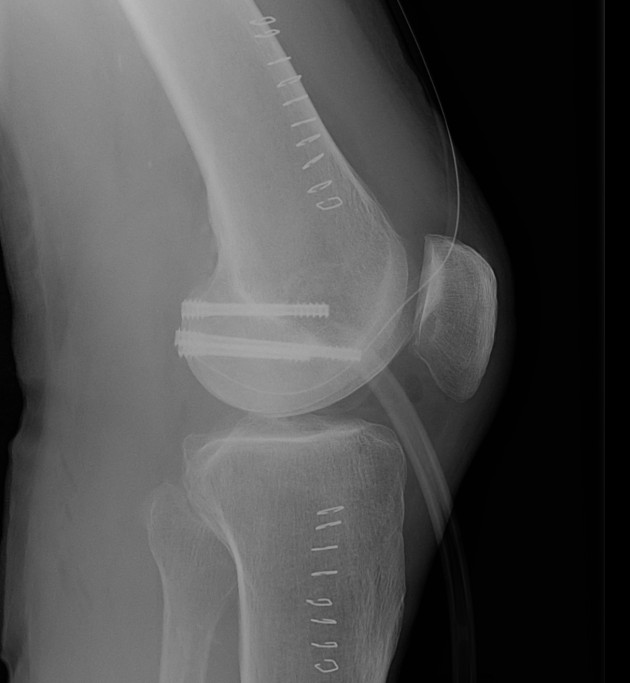

Hoffa Fracture Xray

Coronal plane fracture of distal femoral condyle

Xray

1. Unicondylar

Lateral femoral condyle > medial femoral condyle

Unicondylar Fixation

1.  AP screws

Hoffa Fracture ORIF APHoffa Fracture Lateral